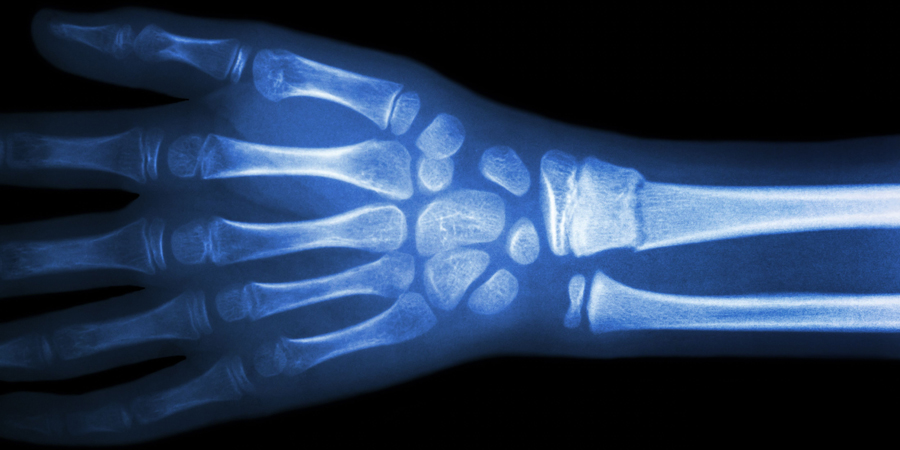

In het artikel 'Toegang tot röntgendiagnostiek op de huisartsenpost' (H&W 6, 2018) beschrijft Rutten de voordelen van toegang tot röntgendiagnostiek op de huisartsenpost (HAP). HAP’s die toegang hadden tot röntgendiagnostiek, verwezen 40% van de patiënten met een mogelijke fractuur naar de SEH; voor HAP’s zonder die toegang was dat 100%. Prachtige resultaten. Maar wat doe je als radiologie of een radioloog niet op elk uur van de dag beschikbaar is? In Zeeuws-Vlaanderen beoordeelt de dienstdoende huisarts zelf de foto’s.